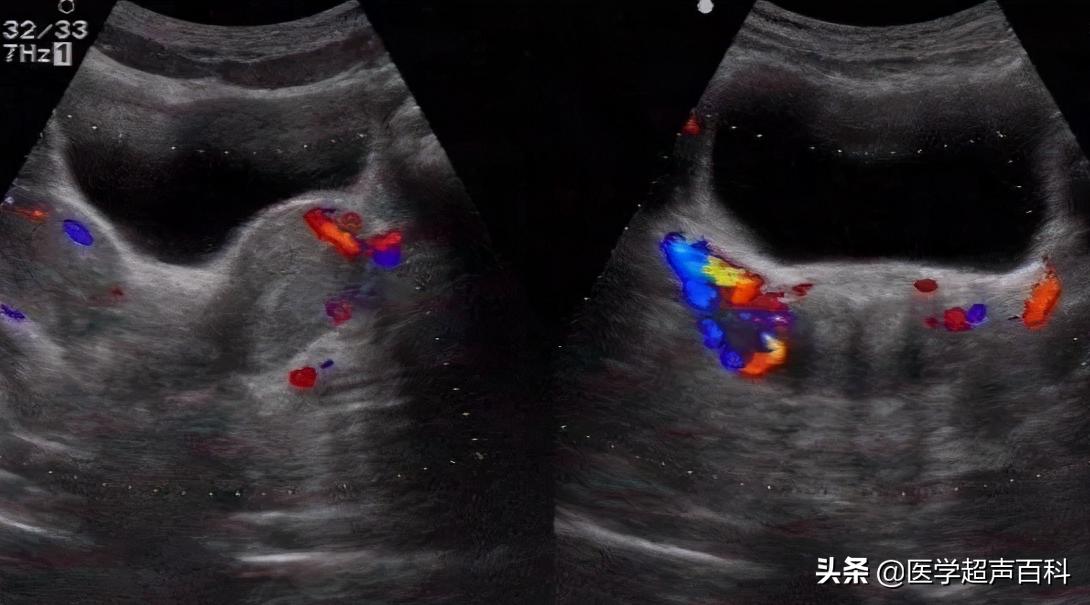

4.双子宫:连续纵切面扫查可见先后显示两个狭长的子宫。宫体及宫底横切面,可显示左右对称的两个子宫,两个子宫均可见各自的内膜回声;宫颈横切面见宫颈横泾增宽,可见两个宫颈管回声。可见双侧卵巢影像。

5.双角子宫:横切扫查近宫底部内膜呈“蝶翅”样表现,子宫底部外缘凹陷呈双角。由宫底向宫体连续扫查时,见两侧内膜逐渐汇聚到一处。

6.纵膈子宫:子宫大小外形正常,宫底横泾较宽,三维超声冠状面内膜呈“V”形为完全纵膈,呈“Y”形为不完全纵膈。